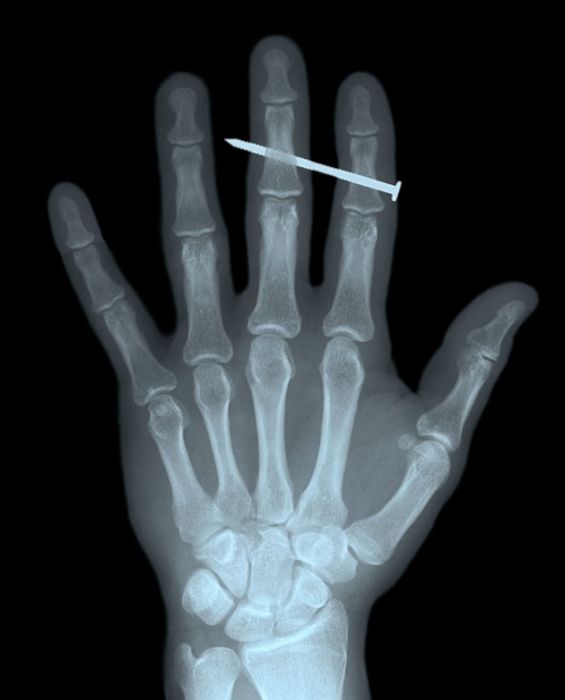

Рентгеновские снимки людей, которые умудрились сами или с чужой помощью разместить внутри своего организма разные посторонние предметы. От вилок и ножей до пуль и бензопилы (!!!). По этическим соображениям обычные снимки таких травм и повреждений выкладывать нельзя, зато рентгеновские можно – на них травмы видны достаточно условно, хоть и очень понятно.